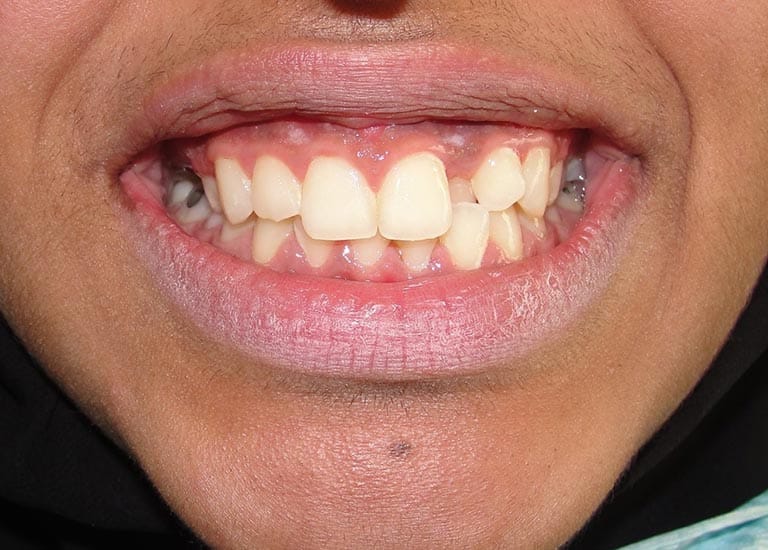

BEFORE

Our young friend suffered from insufficient spaces for her teeth to align properly, which caused her a reverse bite in some of the front teeth.

She also suffered from a severe gummy smile and had a gap resulting from the extraction of an upper molar.